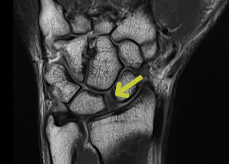

Skafolunat bağ yaralanmaları en sık görülen el bileği yaralanmalarıdır. Bu bağ skafoid ve lunat kemiği bir arada tutar. Bu bağın bozulması skafolunat instabilitesine neden olur. Geç aşamalarda skafoid ve lunat kemik arasında bir boşluk oluşur ve skafolunat ayrışması olarak bilinir.